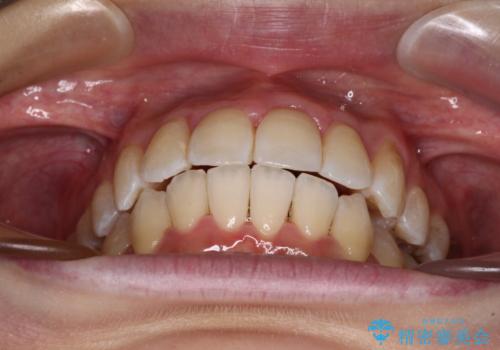

1. 開始前

1. 【モニター】急速拡大装置 狭い歯列を拡大してワイヤー装置で短期間治療の治療前